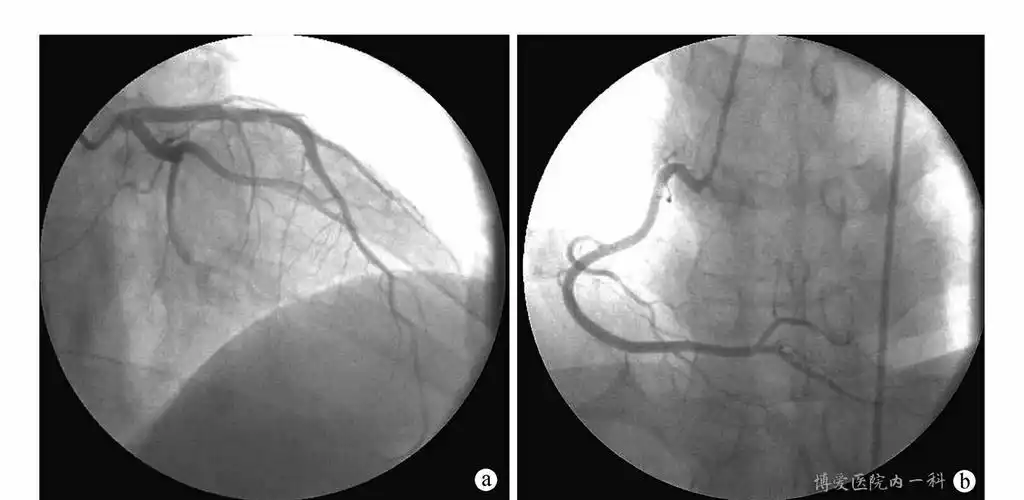

博爱医院内一科冠状动脉造影